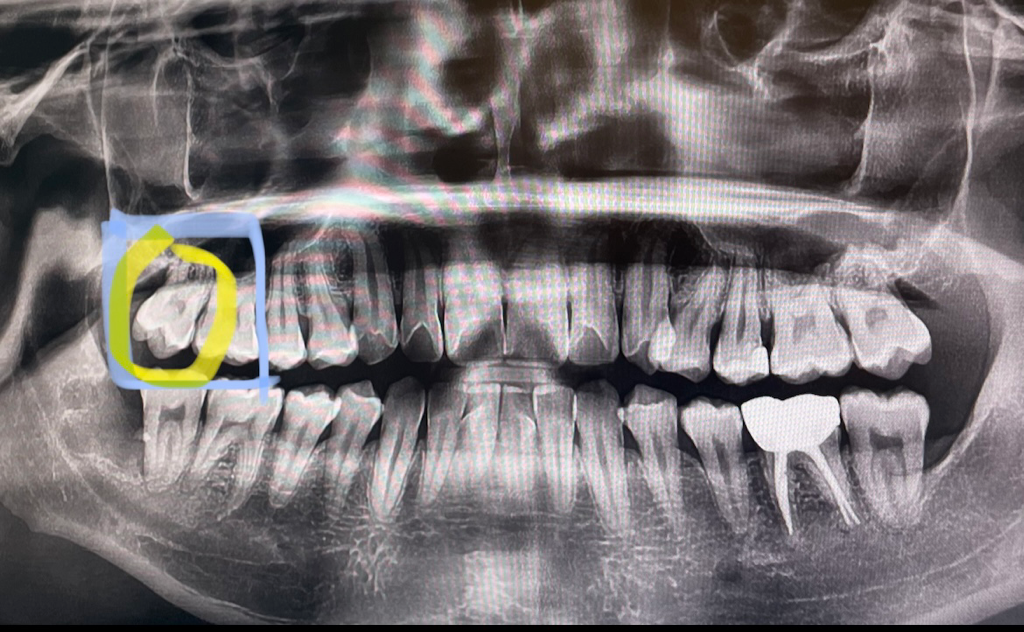

질기거나 딱딱한 음식을 먹을때 오른쪽 윗어금니 혹은 그 옆 치아 부분에 불편한 통증이 있습니다. 찌릿 하거나 저린 느낌의 통증은 아니고 묵직(?) 눌리는 느낌의 압통같은 통증이에요. 평상시나 일상적인 식사를 할때는 통증이 없고 뜨겁거나 차가운 음식이나 액체를 먹을때도 이렇다 할 통증은 없습니다.

위와같은 증상 관련해서 세군데의 치과를 가봤는데 모두 충치나 기타 특이사항은 없으니 지켜보자 말씀 하셨는데 여전히 질기거나 딱딱한 음식을 먹을때 편한 식사가 안 될 정도로 불편한 통증이 있습니다.. 선생님들 말씀으로는 한군데는 치아가 사선으로 자람으로 인해 씹는 과정에서 통증이 있을 수 있다 했고, 한군데는 엑스레이상 저 부분의 높이 차이로 교합시 통증이 생길 수 있으니 정 불편하면 어금니 부분 치아를 살짝 갈아내자 하셨습니다. 근데 여태 괜찮다가 갑자기 왜 이러는지 모르겠어요. 특이사항으로는 6월 8일에 오른쪽 아래 매복사랑니 발치를 했고 사랑니 발치 1주 전부터(사랑니 통증 때문) 발치 후 1주일 정도는 오른쪽으로 식사 하지 않았습니다.

아래 엑스레이 사진 첨부하겠습니다 ㅠㅠ

** 엑스레이상 어금니가 있는 사진은 올 초 겨울이고, 나머지 두장은 이번에 진료볼때 사진입니다.

사진상으로 보면 잇몸뼈가 많이 녹아 잇는것처럼 보입니다. 치아가 흔들린다면 그게 원인일수도 있습니다. 만약 흔들리지 않는데 치아가 불편하다면 치아에 금이갓을 가능성이 높습니다.